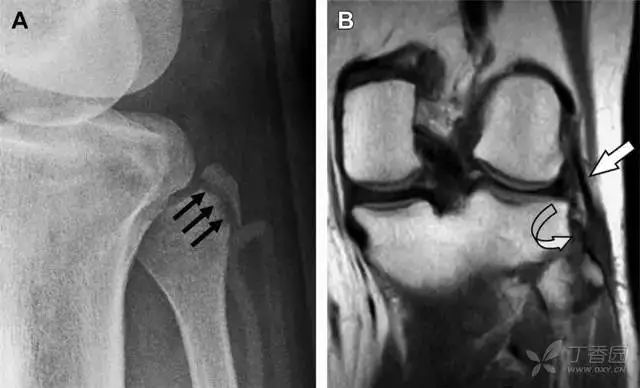

09股骨外侧髁凹陷征

图 2 扭伤后的股骨外侧髁凹陷征

A 侧位片示股骨外侧髁凹陷。B MRI 矢状位 T2 加权像示股骨外侧髁及胫骨后外侧骨挫伤(空箭头)。胫骨近端随着后交叉韧带撕裂发生移位,露出外侧半月板的后角(弧形箭头)。

10胫骨后外侧碎片骨折

胫骨后外侧小片骨皮质的压缩性骨折,可能是旋转移位损伤的唯一证据(图 3)。这种骨折在常规膝关节平片很难发现,若怀疑存在骨折,行下肢内旋斜位片检查可诊断。

图 3 胫骨后外侧碎片骨折

A 正位片示胫骨后外侧处可见一压缩骨折的小碎片(方框)。这是胫骨撞击股骨外侧髁旋转移位时所致。B 另一位患者的 MRI 矢状位 T1 加权像示胫骨后外侧骨折碎片(箭头)。